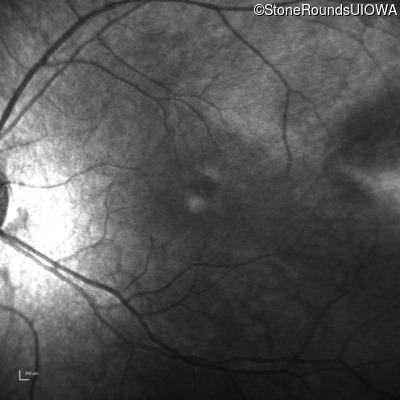

Congenital Stationary Synaptic Dysfunction (IA2g)

Age at visit:

8 years

OD

OS

20/80 sc

20/80 -1 sc